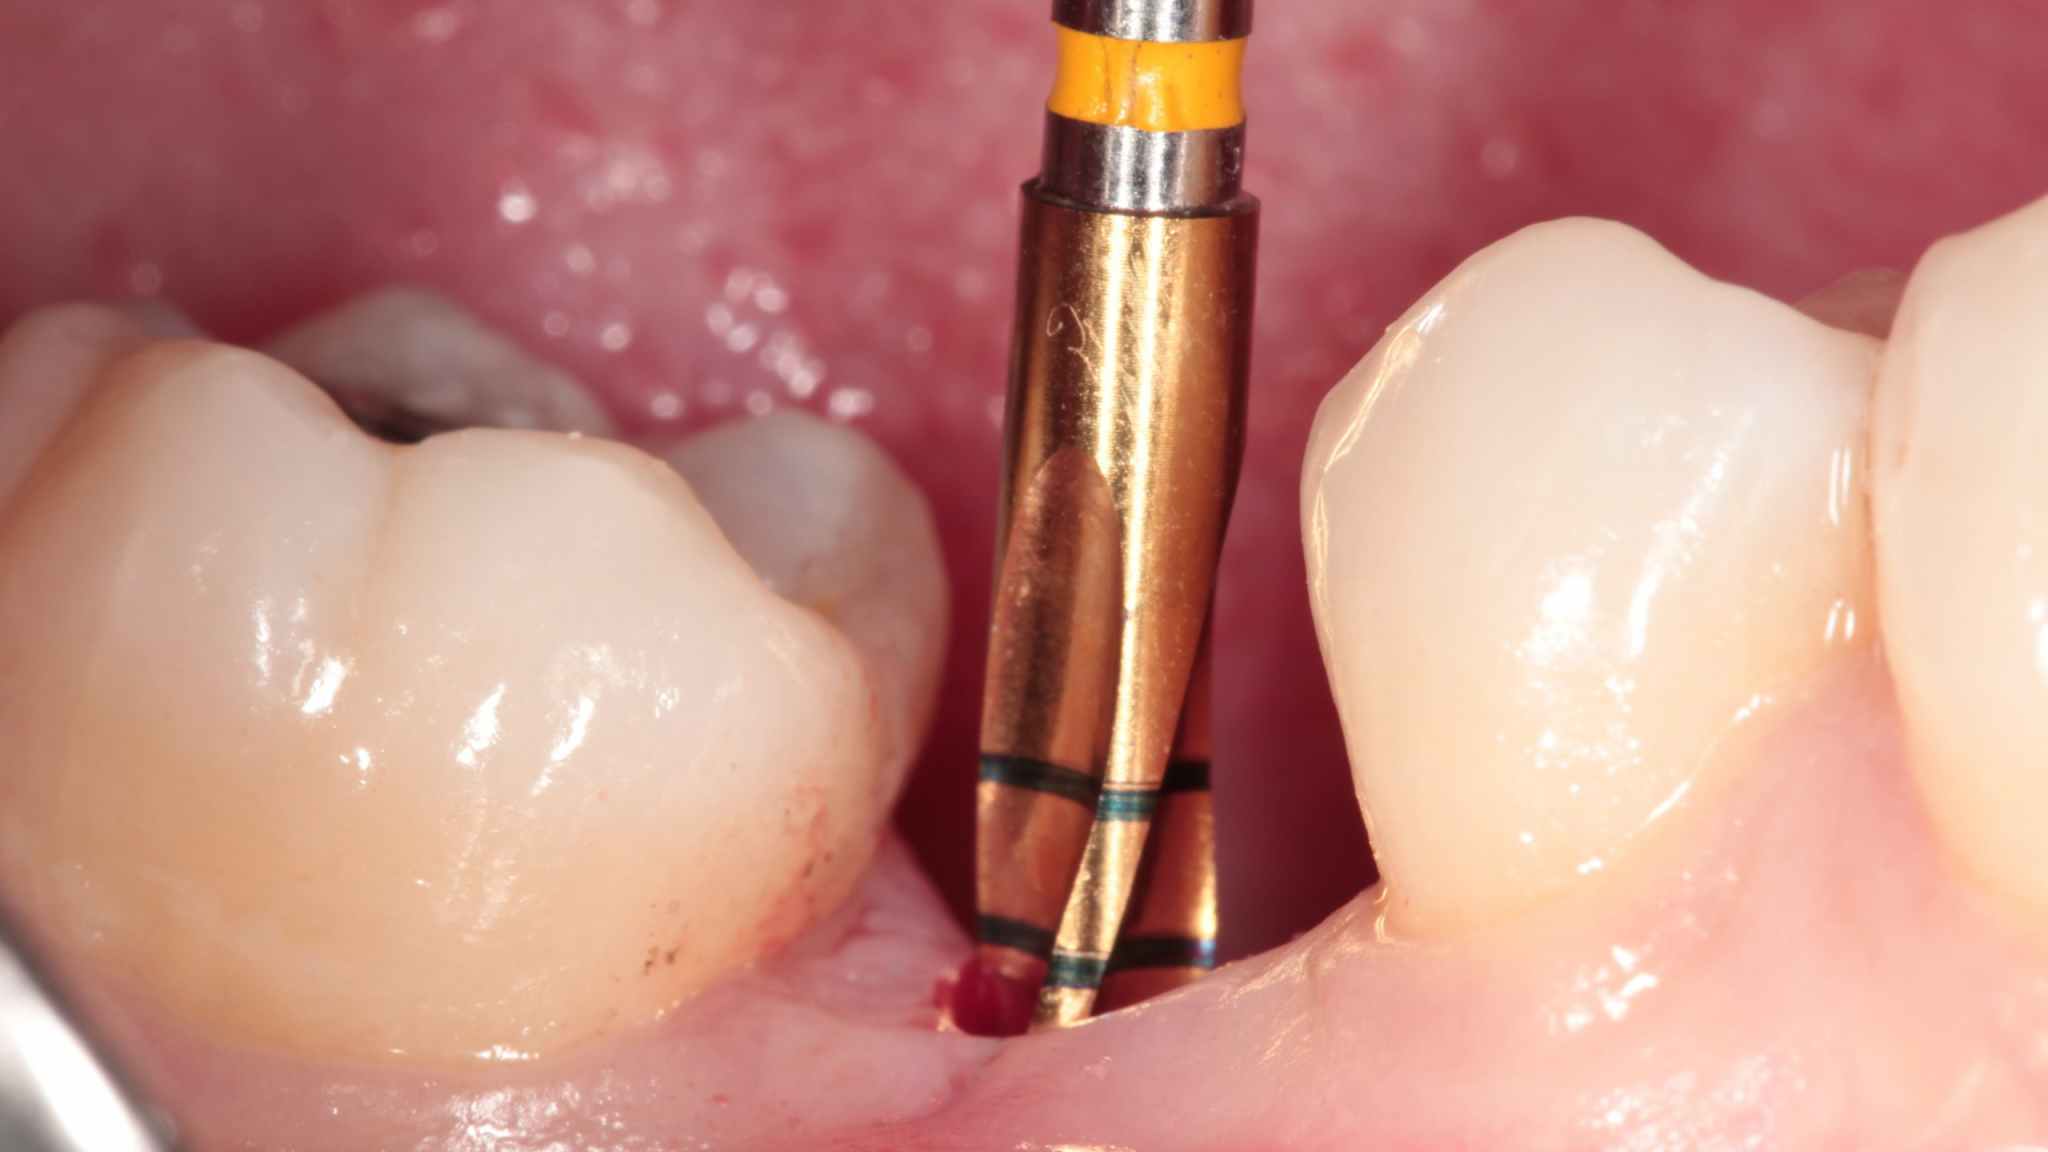

Position the surgical guide, then incise gingiva and drill pilot hole. Check depth and condition of pilot hole.

Profile drill for implant. Insert the implant.